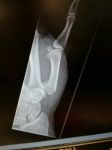

Horse v Motorbike

Final score:

Horsre 4 TTR 1

Not really ok, damage to front of my bike,

double open fracture to right foearm, broken and dislocated left thumb, stitches to right knee!

Loose horse ran straight over me even though i had stopped in the road!